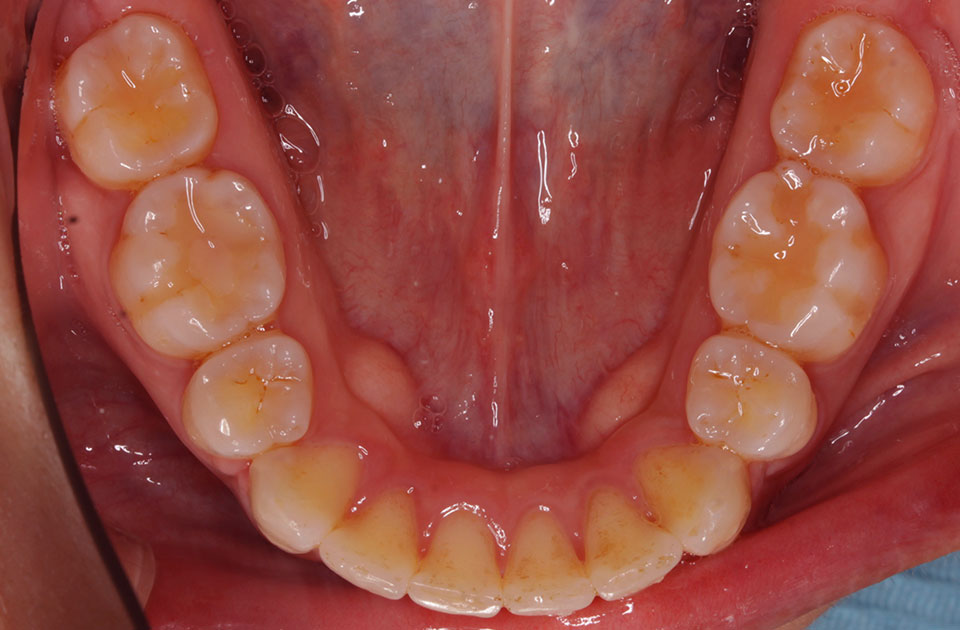

矯正前 下顎